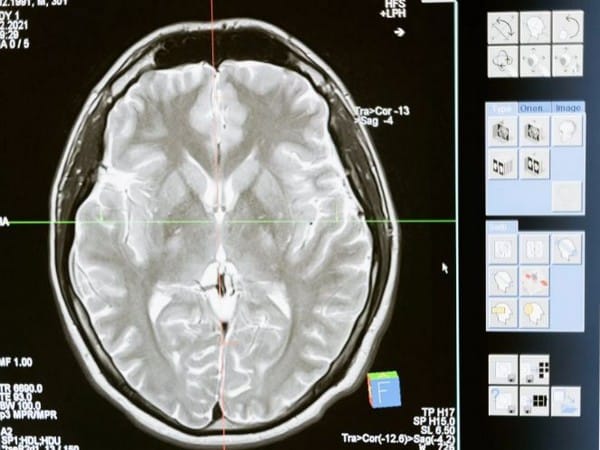

Washington [US], December 1 (ANI): Neuroscientists discovered that the adult brain contains millions of ‘silent synapses’ immature connections between neurons that remain inactive until they’re recruited to help form new memories.

Until now, it was believed that silent synapses were present only during early development when they help the brain learn the new information that it’s exposed to early in life. However, a new MIT study revealed that in adult mice, about 30 per cent of all synapses in the brain’s cortex are silent.

The existence of these silent synapses may help explain how the adult brain can continually form new memories and learn new things without modifying existing conventional synapses, the researchers say.